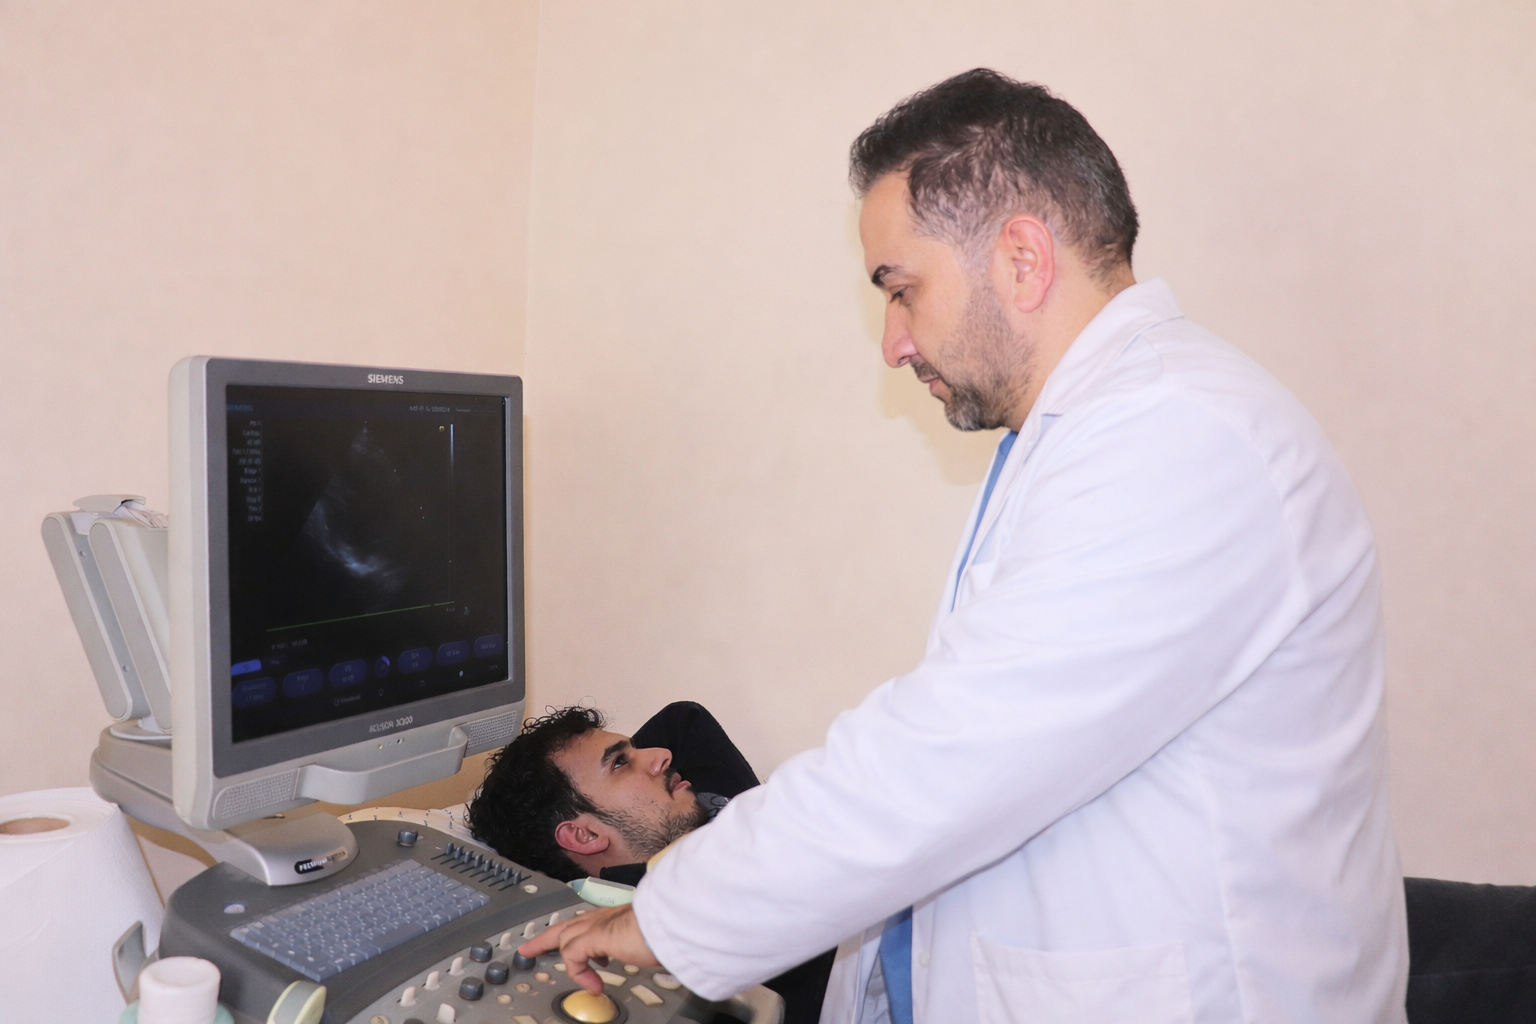

Read MoreEchocardiography

Echocardiography is a non-invasive imaging technique that uses ultrasound waves to create …

Read MoreUltrasound

Ultrasound is a safe, non-invasive medical imaging technique that uses high-frequency sound …